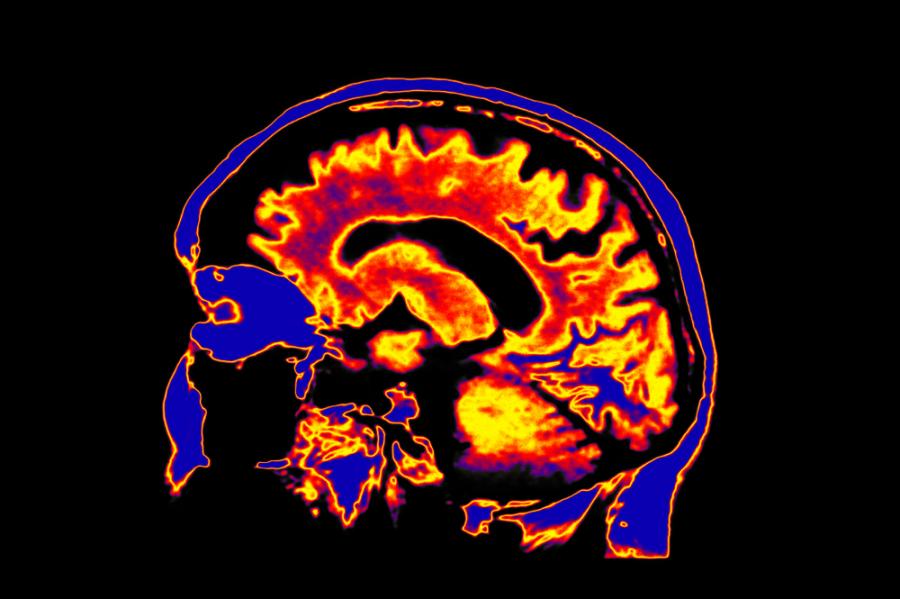

Учени от университетите в Манчестър и Окланд са открили поразяващи разлики в нивата на металите в мозъка на пациенти с болестта на Хънтингтън, вид деменция, в сравнение с контролна група със здрава тъкан, съобщава сайтът Medical Xpress.

Областите с различни нива на невродегенерация са изследвани с помощта на най-съвременната технология, наречена масспектрометрия с индуктивно свързана плазма.